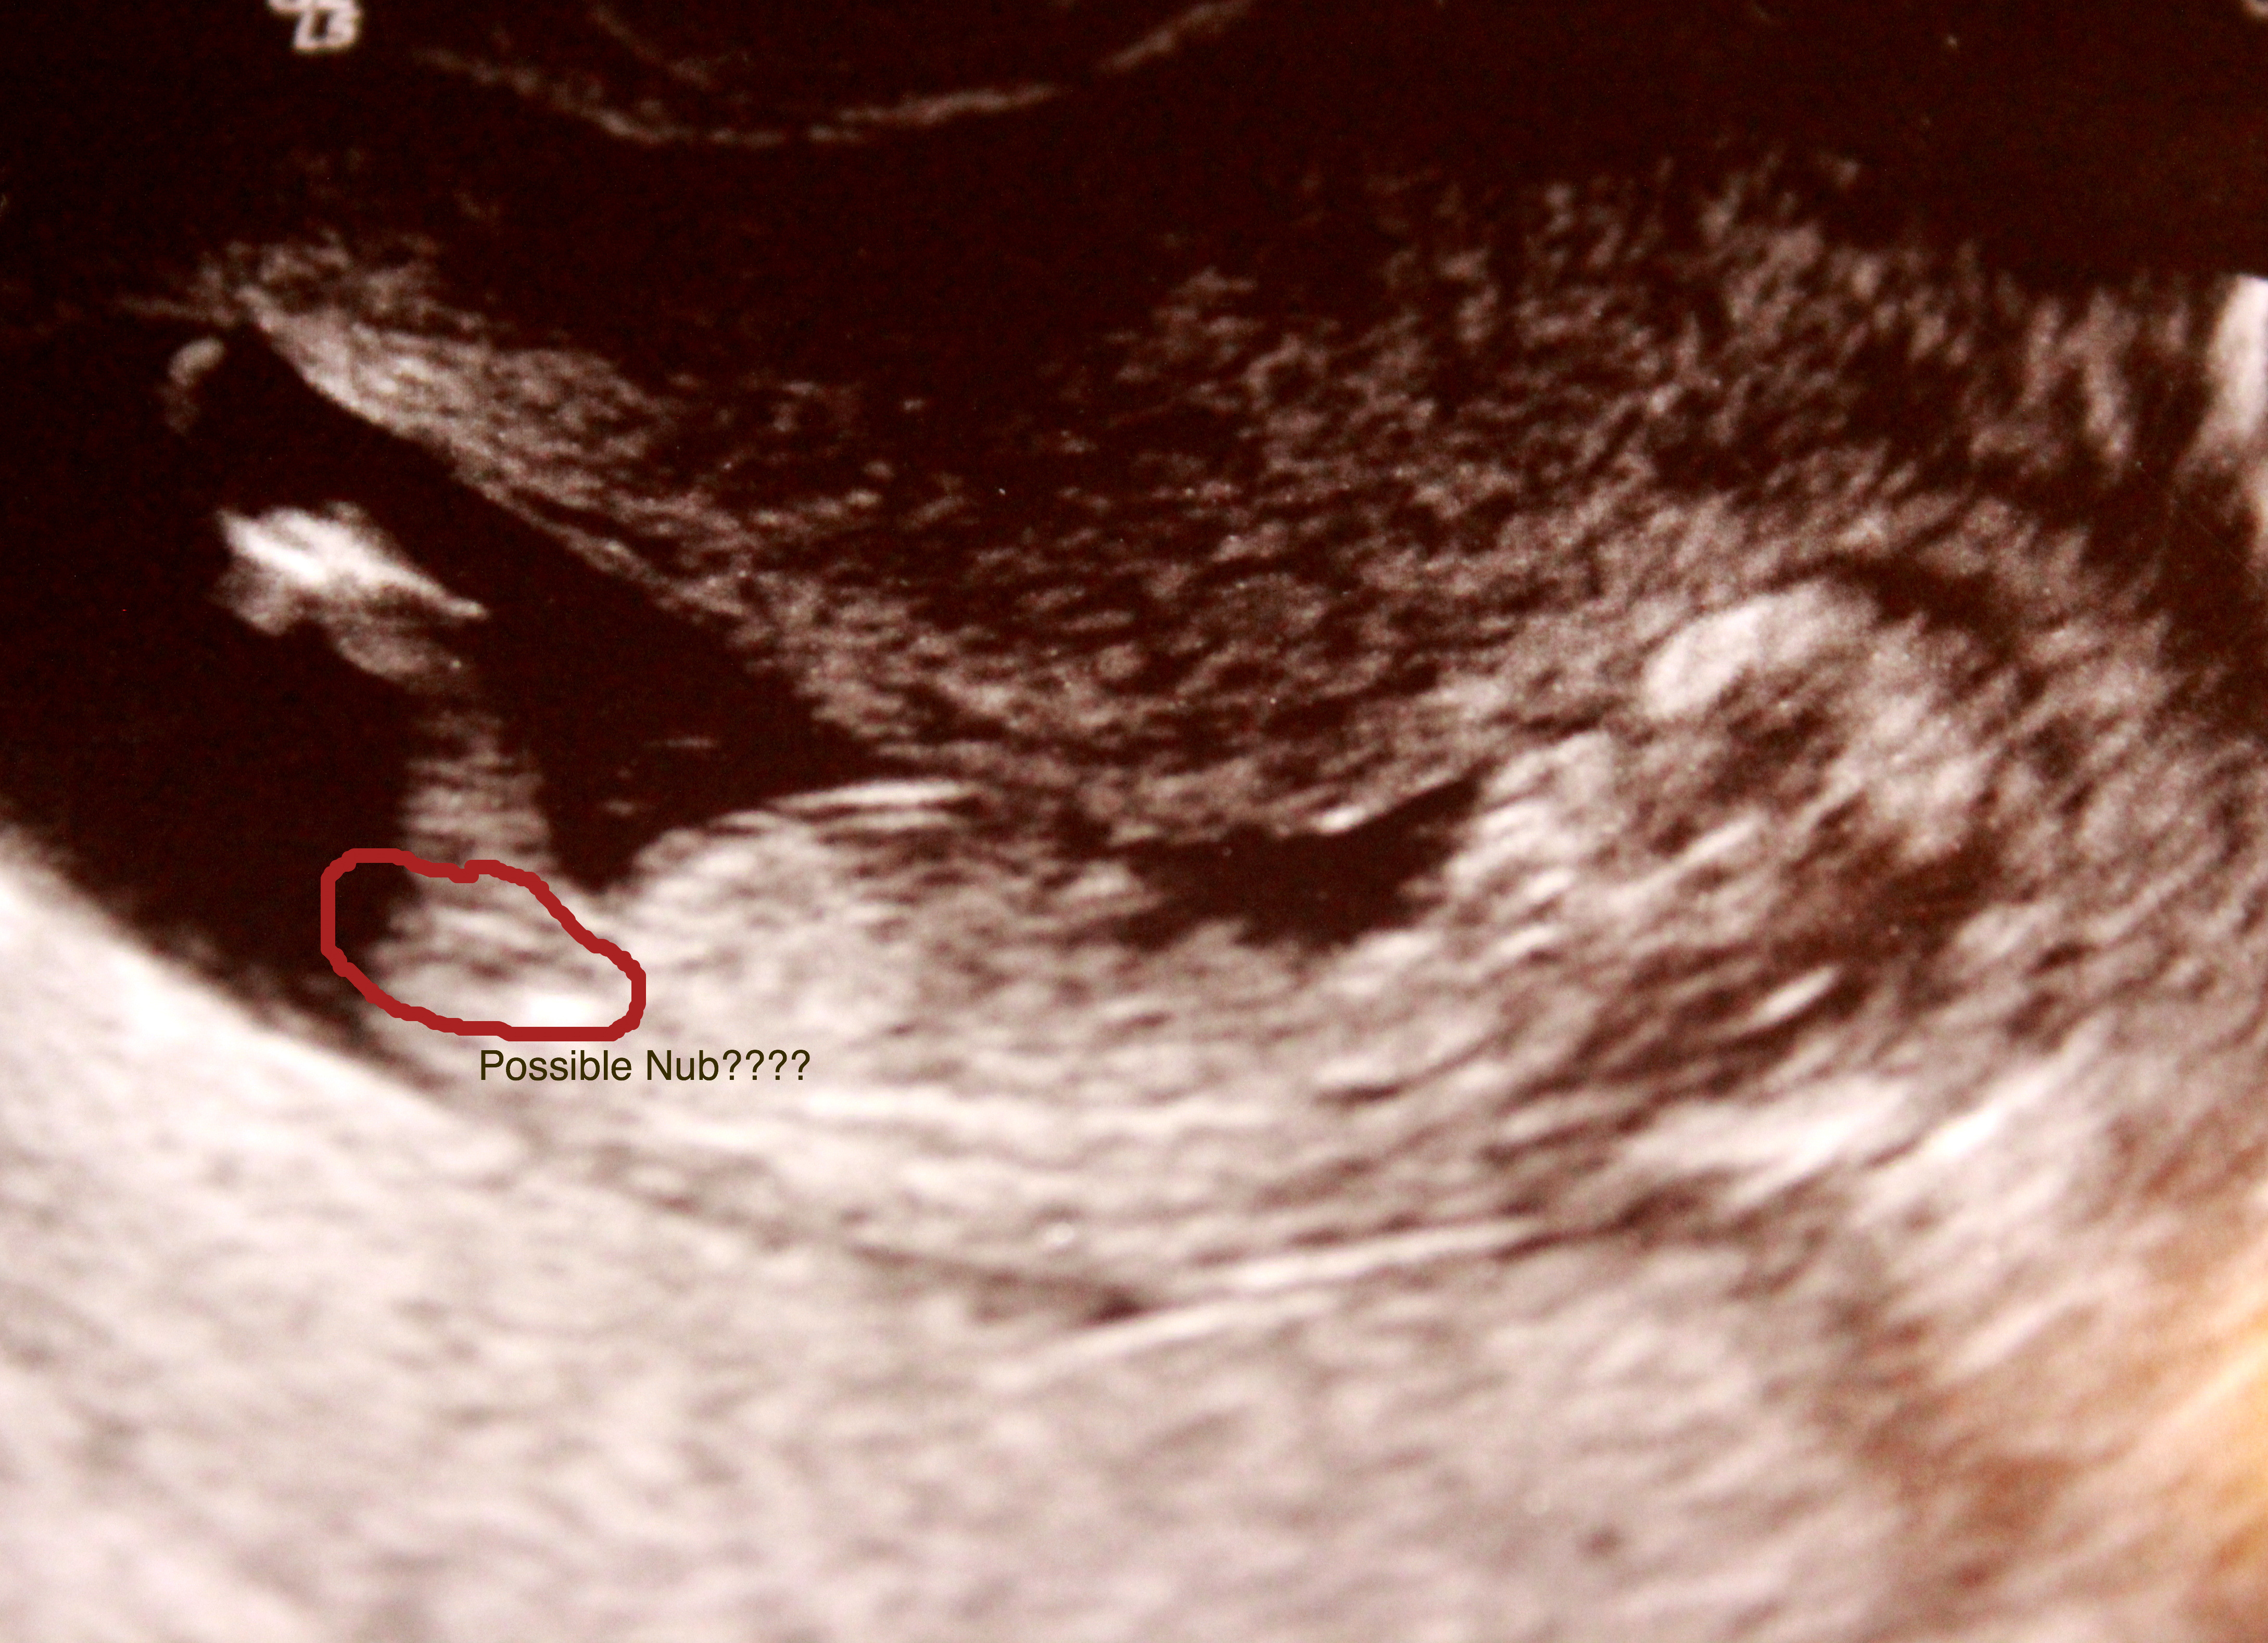

Be gentle but truthful, the doc gave her opinion of BOY so I'm trying to prepare for that. These are the only pics I got and I don't think its the full nub, but I don't know if you need more than that. In the scan I saw a long forked nub but didn't get a pic of it. I couldn't tell the angle though when I saw the complete nub!

I drew on how I remembered the nub lol